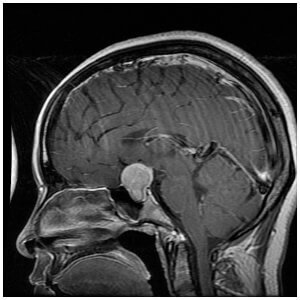

При підозрі на порушення функціонування гіпофіза необхідно відвідати лікаря-ендокринолога. На підставі анамнезу і скарг пацієнта він призначить обстеження. Найбільш простим способом виявити аденому гіпофіза є рентгенівський знімок. Також показано визначення концентрації гормонів у крові, томограма або магнітно-резонансна томограма. При підвищеному діурезі необхідно дослідження змісту вазопресину.